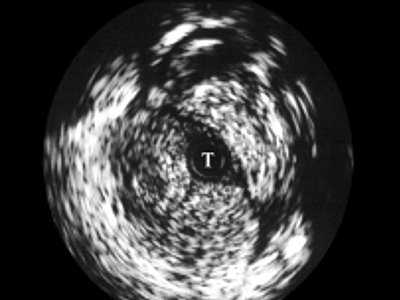

При интрауретральной ультрасонографии в неизмененных отделах мужской уретры по мере проведения датчика мы определяли головку полового члена, губчатое тело, кавернозные тела с окружающими их оболочками, сосуды. В более широком луковичном отделе регистрировались спонгиозная ткань с более тонкой стенкой и прикрепляющимися к ней мышцами (рис. 2).

Рис. 2. Эхограмма нормального луковичного отдела уретры, Т - трансдуктор.